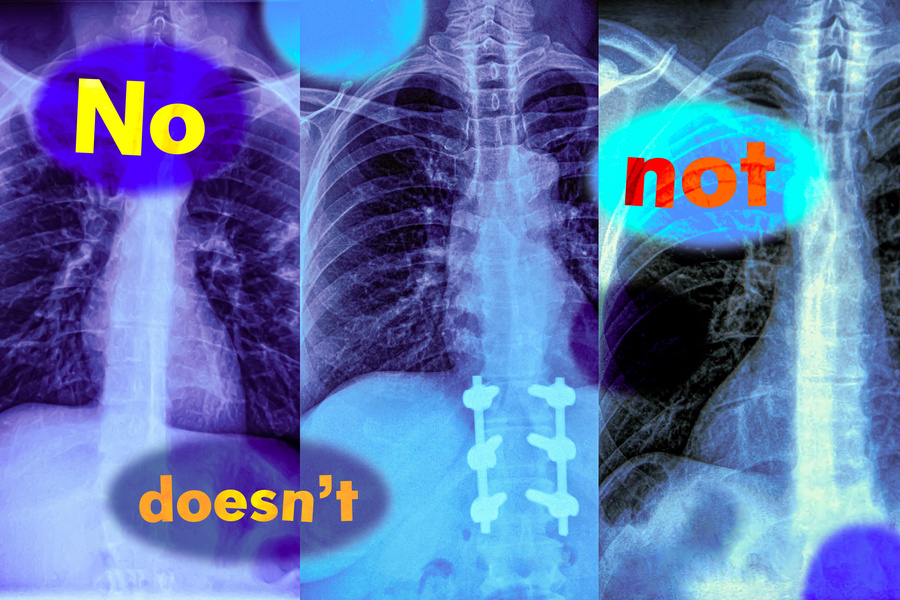

Представьте: врач смотрит на рентген и видит — «опухоль не обнаружена». Чтобы ускорить работу, он подключает ИИ-модель, анализирующую изображения и тексты. Та выдает похожие случаи... но включает в выборку и те, где опухоль была. Почему? Потому что модель проигнорировала слово «не», а это значит, что диагноз может быть неверным.

• BioMedCLIP теряла до 33% точности при работе с простыми утверждениями вроде «есть затемнение лёгких» vs «нет затемнения».